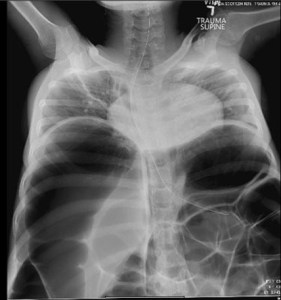

ED abdominal images and workup:

Significant lab results included a non-anion gap metabolic acidosis.

Figure 3. AP abdominal plain film obtained in the ED.